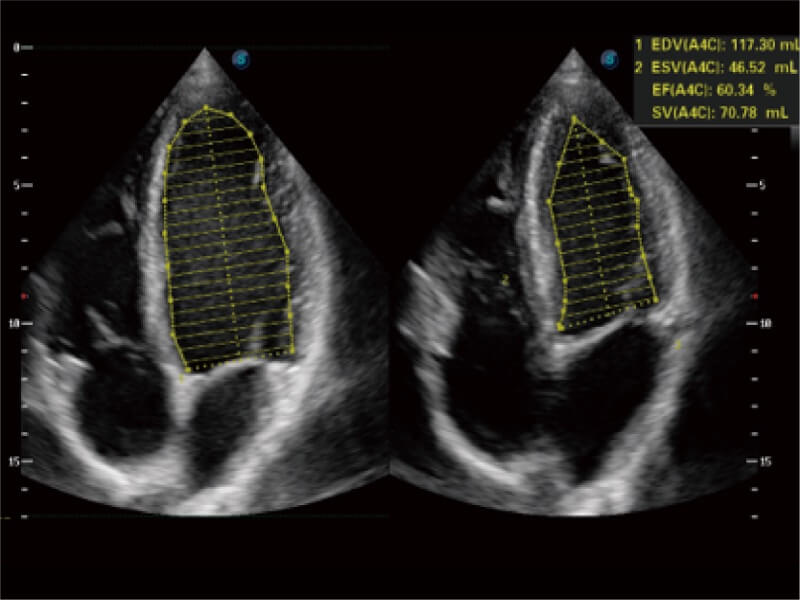

能夠基于左心室壁追蹤和辛普森法,自動計算射血分?jǐn)?shù),支持多個可移動點描跡,與手動測量相比,極大節(jié)省了動物醫(yī)生的時間和精力。